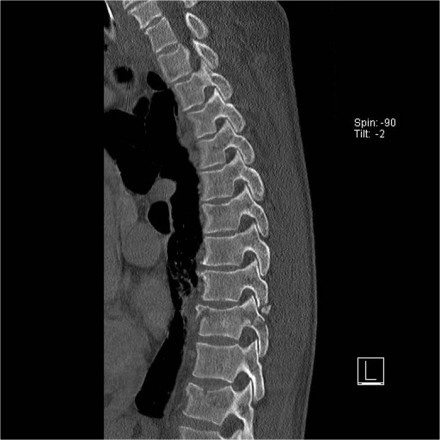

Rigid spine

Patients with a rigid spine (such as in ankylosing spondylitis, DISH and rheumatoid arthritis) are more susceptible to spinal fractures, even after minimal trauma (6).

Ossification of the spinal ligaments and calcification of the annulus fibrosus alter the biomechanics of the spine, creating long lever arms and limiting the ability to absorb even minor impacts.

The bone is usually very osteoporotic.

The images are of a patient with a typical bamboo spine as a result of ankylosing spondylitis.

After a fall on his back no fracture was seen on the x-rays.

However the CT shows a thin fracture line through the anterior side of the vertebral body and also through the spinous process.